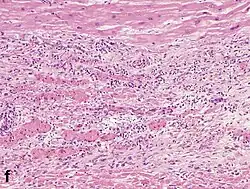

Under the microscope, myocardial infarction presents as a circumscribed area of ischemic, coagulative necrosis (cell death). On gross examination, the infarct is not identifiable within the first 12 hours.[22]

Although earlier changes can be discerned using electron microscopy, one of the earliest changes under a normal microscope are so-called wavy fibers.[23] Subsequently, the myocyte cytoplasm becomes more eosinophilic (pink) and the cells lose their transversal striations, with typical changes and eventually loss of the cell nucleus.[24] The interstitium at the margin of the infarcted area is initially infiltrated with neutrophils, then with lymphocytes and macrophages, who phagocytose ("eat") the myocyte debris. The necrotic area is surrounded and progressively invaded by granulation tissue, which will replace the infarct with a fibrous (collagenous) scar (which are typical steps in wound healing). The interstitial space (the space between cells outside of blood vessels) may be infiltrated with red blood cells.[22]

| Neutrophil infiltration | 12–24 h | 1–3 days | 5–7 days |

| Macrophages and lymphocytes | 3–5 days | 5–10 days (including 'siderophages') | 10 days to 2 months |